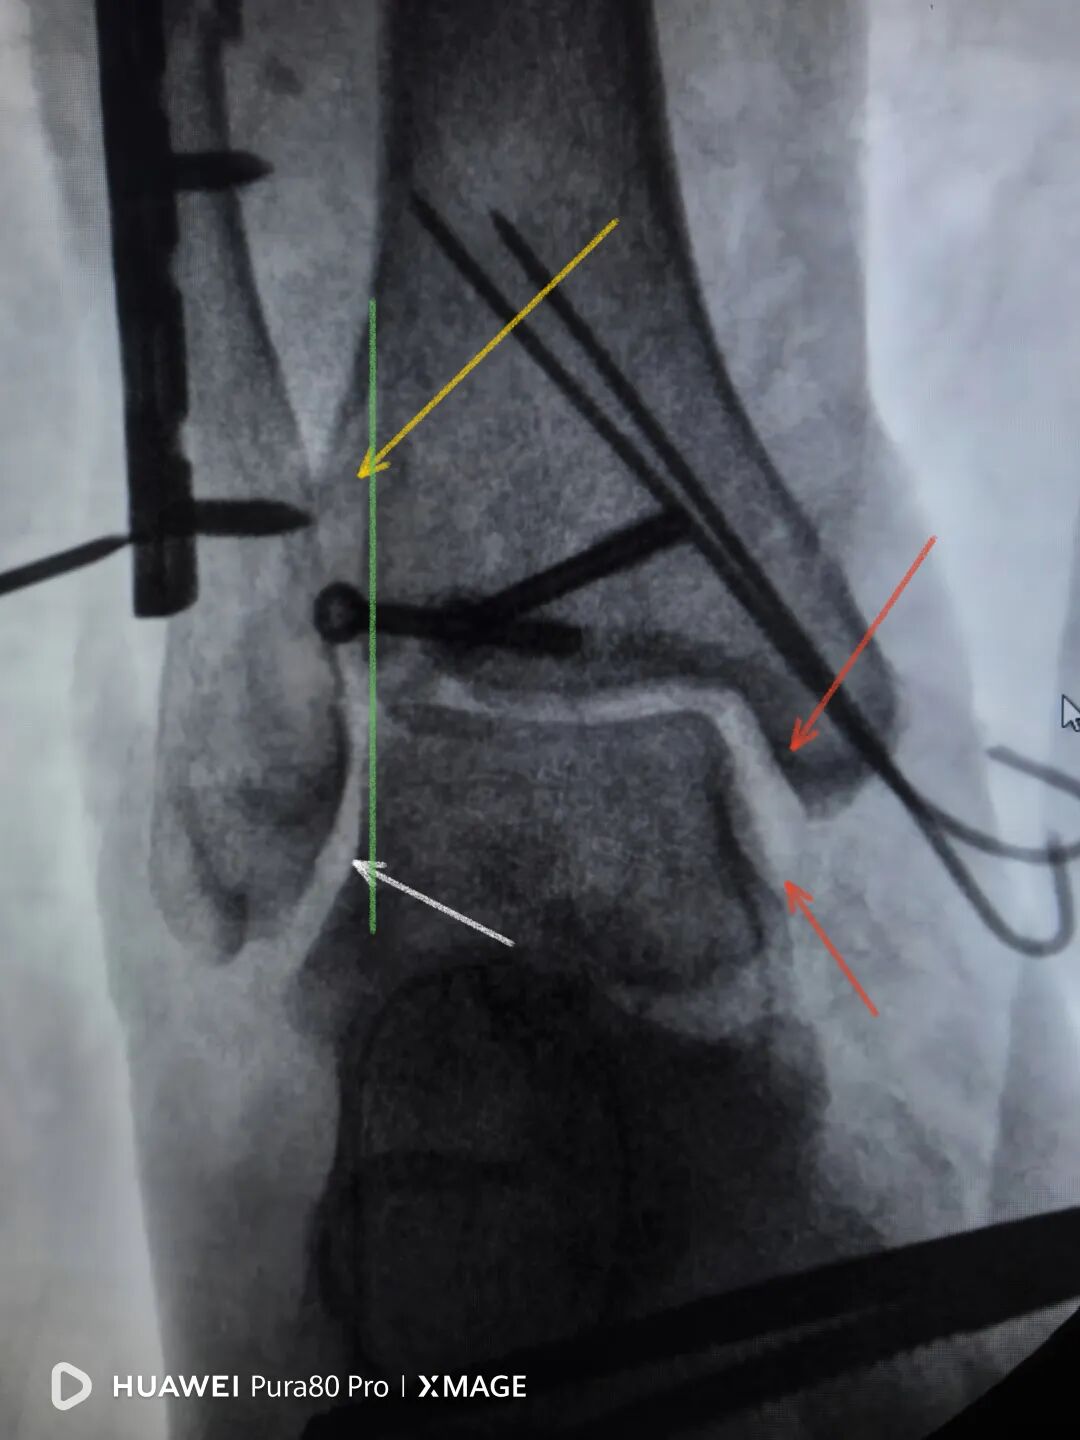

最后做下胫腓

两个位置螺钉固定

下胫腓关节复位

内踝间隙恢复